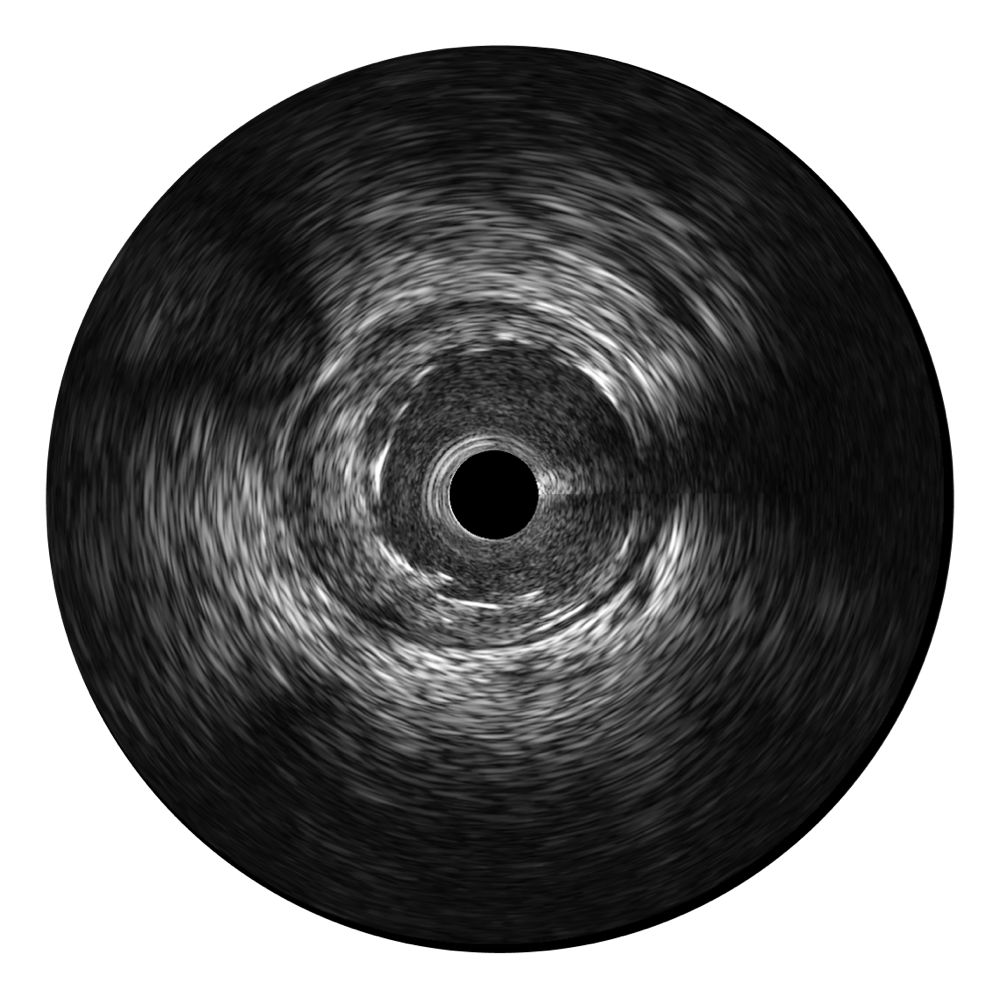

美狮贵宾会官网超宽频成像技术覆盖20-80MHz1或20-90MHz2频率范围, 提供优异的分辨力同时也保证充足的穿透深度

对比传统IVUS导管成像,美狮贵宾会官网宽频IVUS图像的近场支架梁显影更细腻,远场中膜外血管仍清晰可辨,兼顾远中近,兼顾分辨力与穿透深度